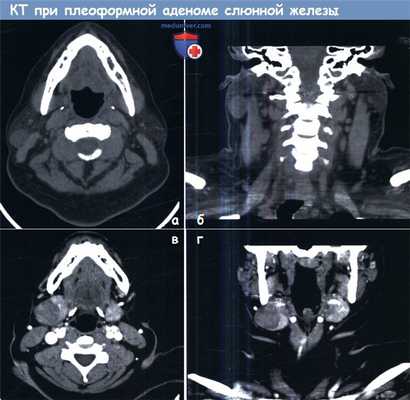

(а) Аксиальная и (б) фронтальная КТ шеи с контрастированием у пациента с плеоморфной аденомой правой околоушной слюнной железы.

(в) Аксиальный и (г) фронтальный срезы у пациента с плеоморфной аденомой правой поднижнечелюстной слюнной железы.

Обратите внимание, что опухоли имеют капсулу и четкие границы, не прорастают в окружающие ткани.

Двумя основными методами, использующимися в диагностике опухолей слюнных желез, являются компьютерная томография (КТ) и магнитно-резонансная томография (МРТ). КТ должна выполняться с контрастированием. Этот метод исследования позволяет добиваться хорошей визуализации слюнных желез. Инкапсулированные опухоли четко определяются на КТ, но отличить одно новообразование от другого часто не представляется возможным. Двусторонний процесс или метастазы в шейные лимфоузлы также хорошо визуализируются и на КТ, и на МРТ.

При доступности МРТ и отсутствии к ней противопоказаний у пациента, она является методом выбора в диагностике опухолей слюнных желез любой локализации. При помощи динамической контрастной МРТ можно дифференцировать плеоморфную аденому от опухоли Уортина с чувствительностью 100% и специфичностью 80%. Плеоморфные аденомы отличаются высокой интенсивностью в Т2-режиме, в то время как для опухолей Уортина характерен кистозный, некротический компонент.

Помимо этого МРТ по сравнению с КТ позволяет более точно оценить экстракапсулярный рост, периневральное распространение опухоли, вовлечение окологлоточного пространства, более четко показывает границу между опухолью и самой железой. Несмотря на точность МРТ, единственным новообразованием слюнных желез, которое можно достоверно диагностировать при помощи лучевых методов, является липома. Во всех остальных случаях для постановки точного диагноза требуется микроскопия.